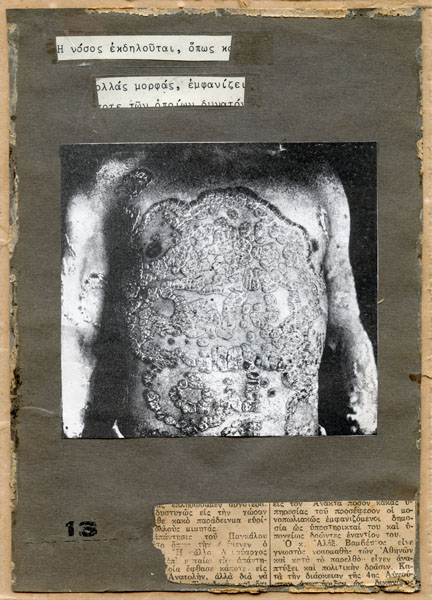

Kon Markogiannis is an experimental photographer-collage artist-visual poet-independent researcher with an interest in themes such as memory, mortality, spirituality, the human condition, the exploration of the human psyche and the evolution of consciousness. He embraces the indexical qualities of photography and its immediate impact on the viewer, but what he is mainly concerned with are the ways "reality" can be transformed. By manipulating the photographic medium and/or combining it with other media he is able to develop a personal and simultaneously transpersonal language which negotiates between subjective art and the photographic document. He sees his work as a kind of weapon against the ephemeral or, as Vilém Flusser would say, a "hunt for new states of things" (Towards a Philosophy of Photography). Kon has been exhibiting his art for many years (mainly in Greece and the UK) and his work has been featured in various books, journals and magazines. His university studies include a BA in Visual Communication Design, an MA in Photography and a Doctorate in Fine Art. He currently lives and works in Thessaloniki, Greece. His website is at konmark.com. He blogs at konmark.blogspot.com.